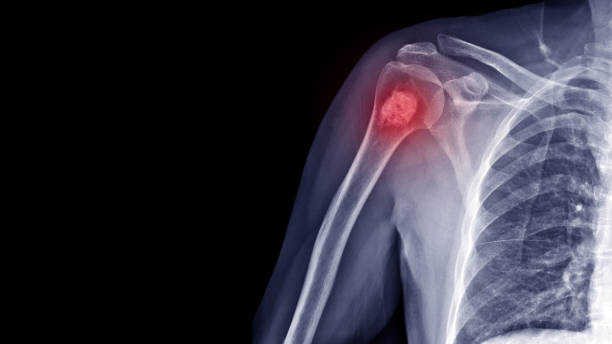

뼈암은 팔이나 다리의 큰 뼈에서 더 흔하지만 신체의 200개의 뼈 중 어느 곳에서나 자랄 수 있습니다. 이것은 성인과 어린이 모두에게 영향을 줄 수 있습니다. 뼈에서 시작되는 암은 흔하지 않습니다. 그러나 공격적일 수 있으므로 조기 발견이 중요합니다.

이차성 골암은 신체의 다른 곳에서 시작되어 뼈로 퍼진 암입니다. 원발성 골암보다 더 흔합니다. 모든 유형의 암이 뼈로 퍼질 수 있지만 가장 흔한 유형은 유방암, 폐암, 신장암, 갑상선암 및 전립선 암입니다. 이차 골암은 일반적으로 엉덩이, 대퇴골, 어깨 또는 척추에서 발견됩니다.

원발성 골암에는 여러 유형이 있습니다. 가장 흔한 것은 골육종으로, 일반적으로 10대 또는 젊은 성인에게 영향을 미치며 긴 뼈의 끝에서 발견됩니다.

두 번째로 흔한 유형은 뼈 끝의 뼈 연골에서 자라는 연골육종입니다. 그것은 일반적으로 40세 이상의 사람들에게 나타나며 골반, 어깨, 무릎, 척추, 팔이나 다리의 상부 또는 갈비뼈에서 발견됩니다.

한편, 의사는 몇 가지의 방법을 사용하여 뼈의 암 단계를 결정할 수 있습니다. 검사에는 조직의 작은 샘플을 분석하여 암을 진단하는 생검, 뼈의 상태를 확인 하는 뼈 스캔, 치료 중 사용을 위한 기준선을 설정하기 위한 혈액검사, 뼈 구조를 자세히 보기 위해 X레이, PET, MRI, CT스캔 등을 포함한 영상 검사가 포함됩니다.